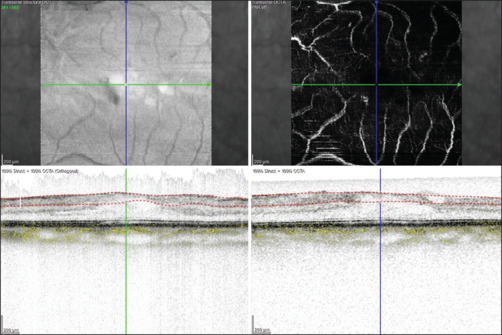

Purpose: This study aims to correlate optical coherence tomography angiography (OCTA)-based retinal microvasculature changes in cases of full-thickness macular hole (FTMH) before and after vitreoretinal surgery and its relation to patient's visual recovery.

Methods: Data of 31 eyes with FTMH were evaluated preoperatively and post-operatively at 6, 12, and 24 weeks for OCTA parameters and compared.

Results: 93.55% eyes (29 eyes) showed improvement in best-corrected visual acuity at 24 weeks. The mean foveal avascular zone (FAZ) significantly reduced from 0.41 ± 0.13 mm2 (preoperatively) to 0.25 ± 0.01 mm2 (postoperatively at 24 weeks). Mean preoperative vessel density (VD) in the superficial vascular plexus (SVP) progressively improved to 24.2% ± 2.2%, 25.2% ± 2.1% and 25.8% ± 2.3% at 6, 12, and 24 weeks respectively from 24.4% ± 2.1% preoperatively (P = 0.0, F = 5.1). The mean VD of foveal region in the SVP significantly improved (P < 0.0, F = 13.9) while that of the parafoveal region did not improve at 24 weeks (P = 0.3, F = 1.2) when compared with its preoperative status. The mean preoperative VD in the deep vascular plexus (DVP) was 20.2% ± 2.6%. It significantly improved at 6, 12, and 24 weeks (20.3% ± 2.4%, 21.8% ± 2.3% and 22.1% ± 2.2%, respectively; P = 0.0, F = 6.9). The mean VD of foveal region and parafoveal region in the DVP showed significant improvement when compared with its preoperative status (P < 0.0, F = 39.3, P < 0.0, F = 13.7).

Conclusion: This study showed reduction in mean FAZ area and improvement in mean VD at SVP and DVP in the macula postoperatively. Routine perioperative OCTA-based documentation of macular vascularity in FTMH may throw a light in cases with anatomico-functional postoperative disparities in future.

Abstract Image